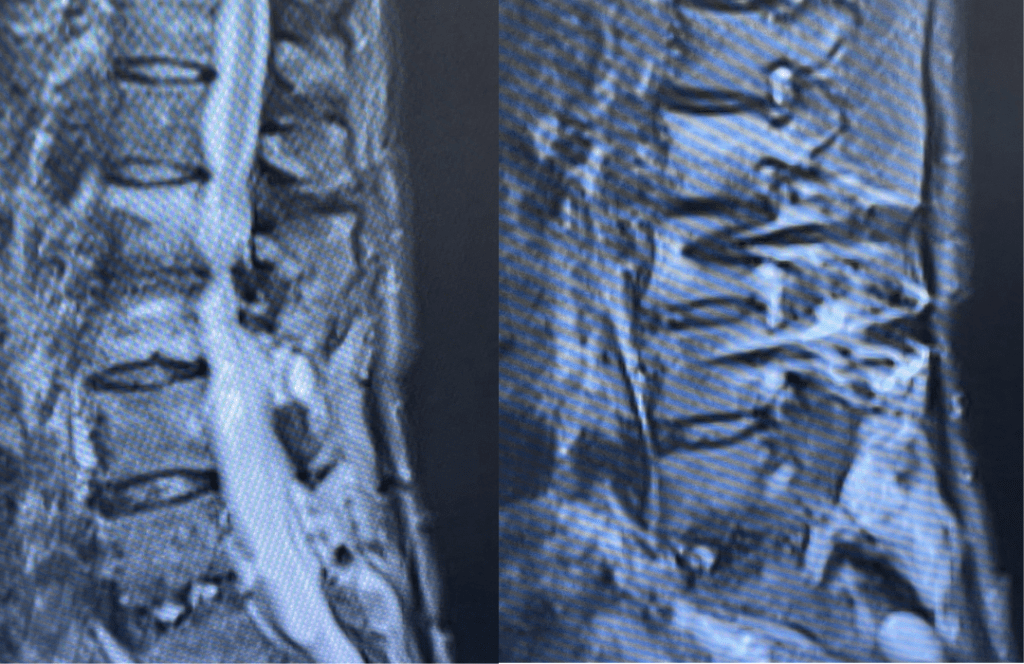

Figures 1a and 1b. Sagittal T2 MRIs of the lumbar spine demonstrating L2-3 stenosis after L3-4 instrumented fusion.